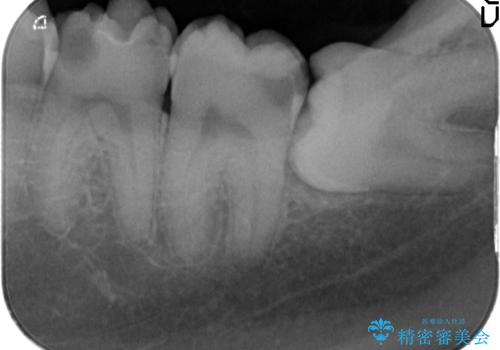

放置した虫歯の治療 親知らずの手前が虫歯

- 詰め物が取れて放置していたとのこと。

虫歯が大きかったため、被せ物(クラウン)としました。

親知らずを抜いてから治療しています。

幸い神経を取らずにすみました。